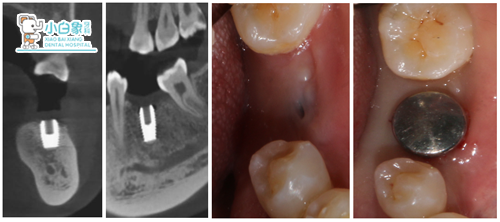

术前 X线 、CT片

术后植入CT